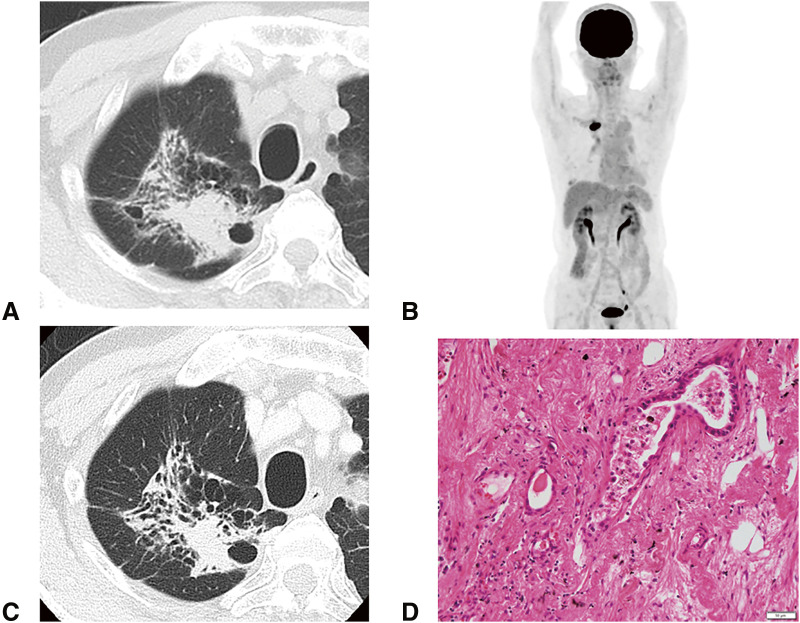

Case presentation: A Japanese man in his 70s was diagnosed with right upper lobe lung adenocarcinoma (cT3N1[#12u]M0, parietal pleural invasion, cStage IIIA), with the programmed death-ligand 1 expression level of <1%. He underwent right upper lobectomy via open thoracotomy followed by 3 cycles of neoadjuvant cisplatin, pemetrexed, and nivolumab. The pathological response rate was 50% and the pathological stage was ypT2bN0M0, ypStage IIA. Seven months after the surgery, he experienced gradually worsening anorexia, fatigue, and hyponatremia. He was diagnosed with pituitary adrenal insufficiency induced by neoadjuvant immunotherapy by the 100 μg corticotropin-releasing hormone stress test. Cardiogenic shock caused by takotsubo cardiomyopathy occurred, and intensive treatment was performed. Steroid therapy was effective, but the physical dysfunction persisted, although no recurrence of lung cancer was observed.